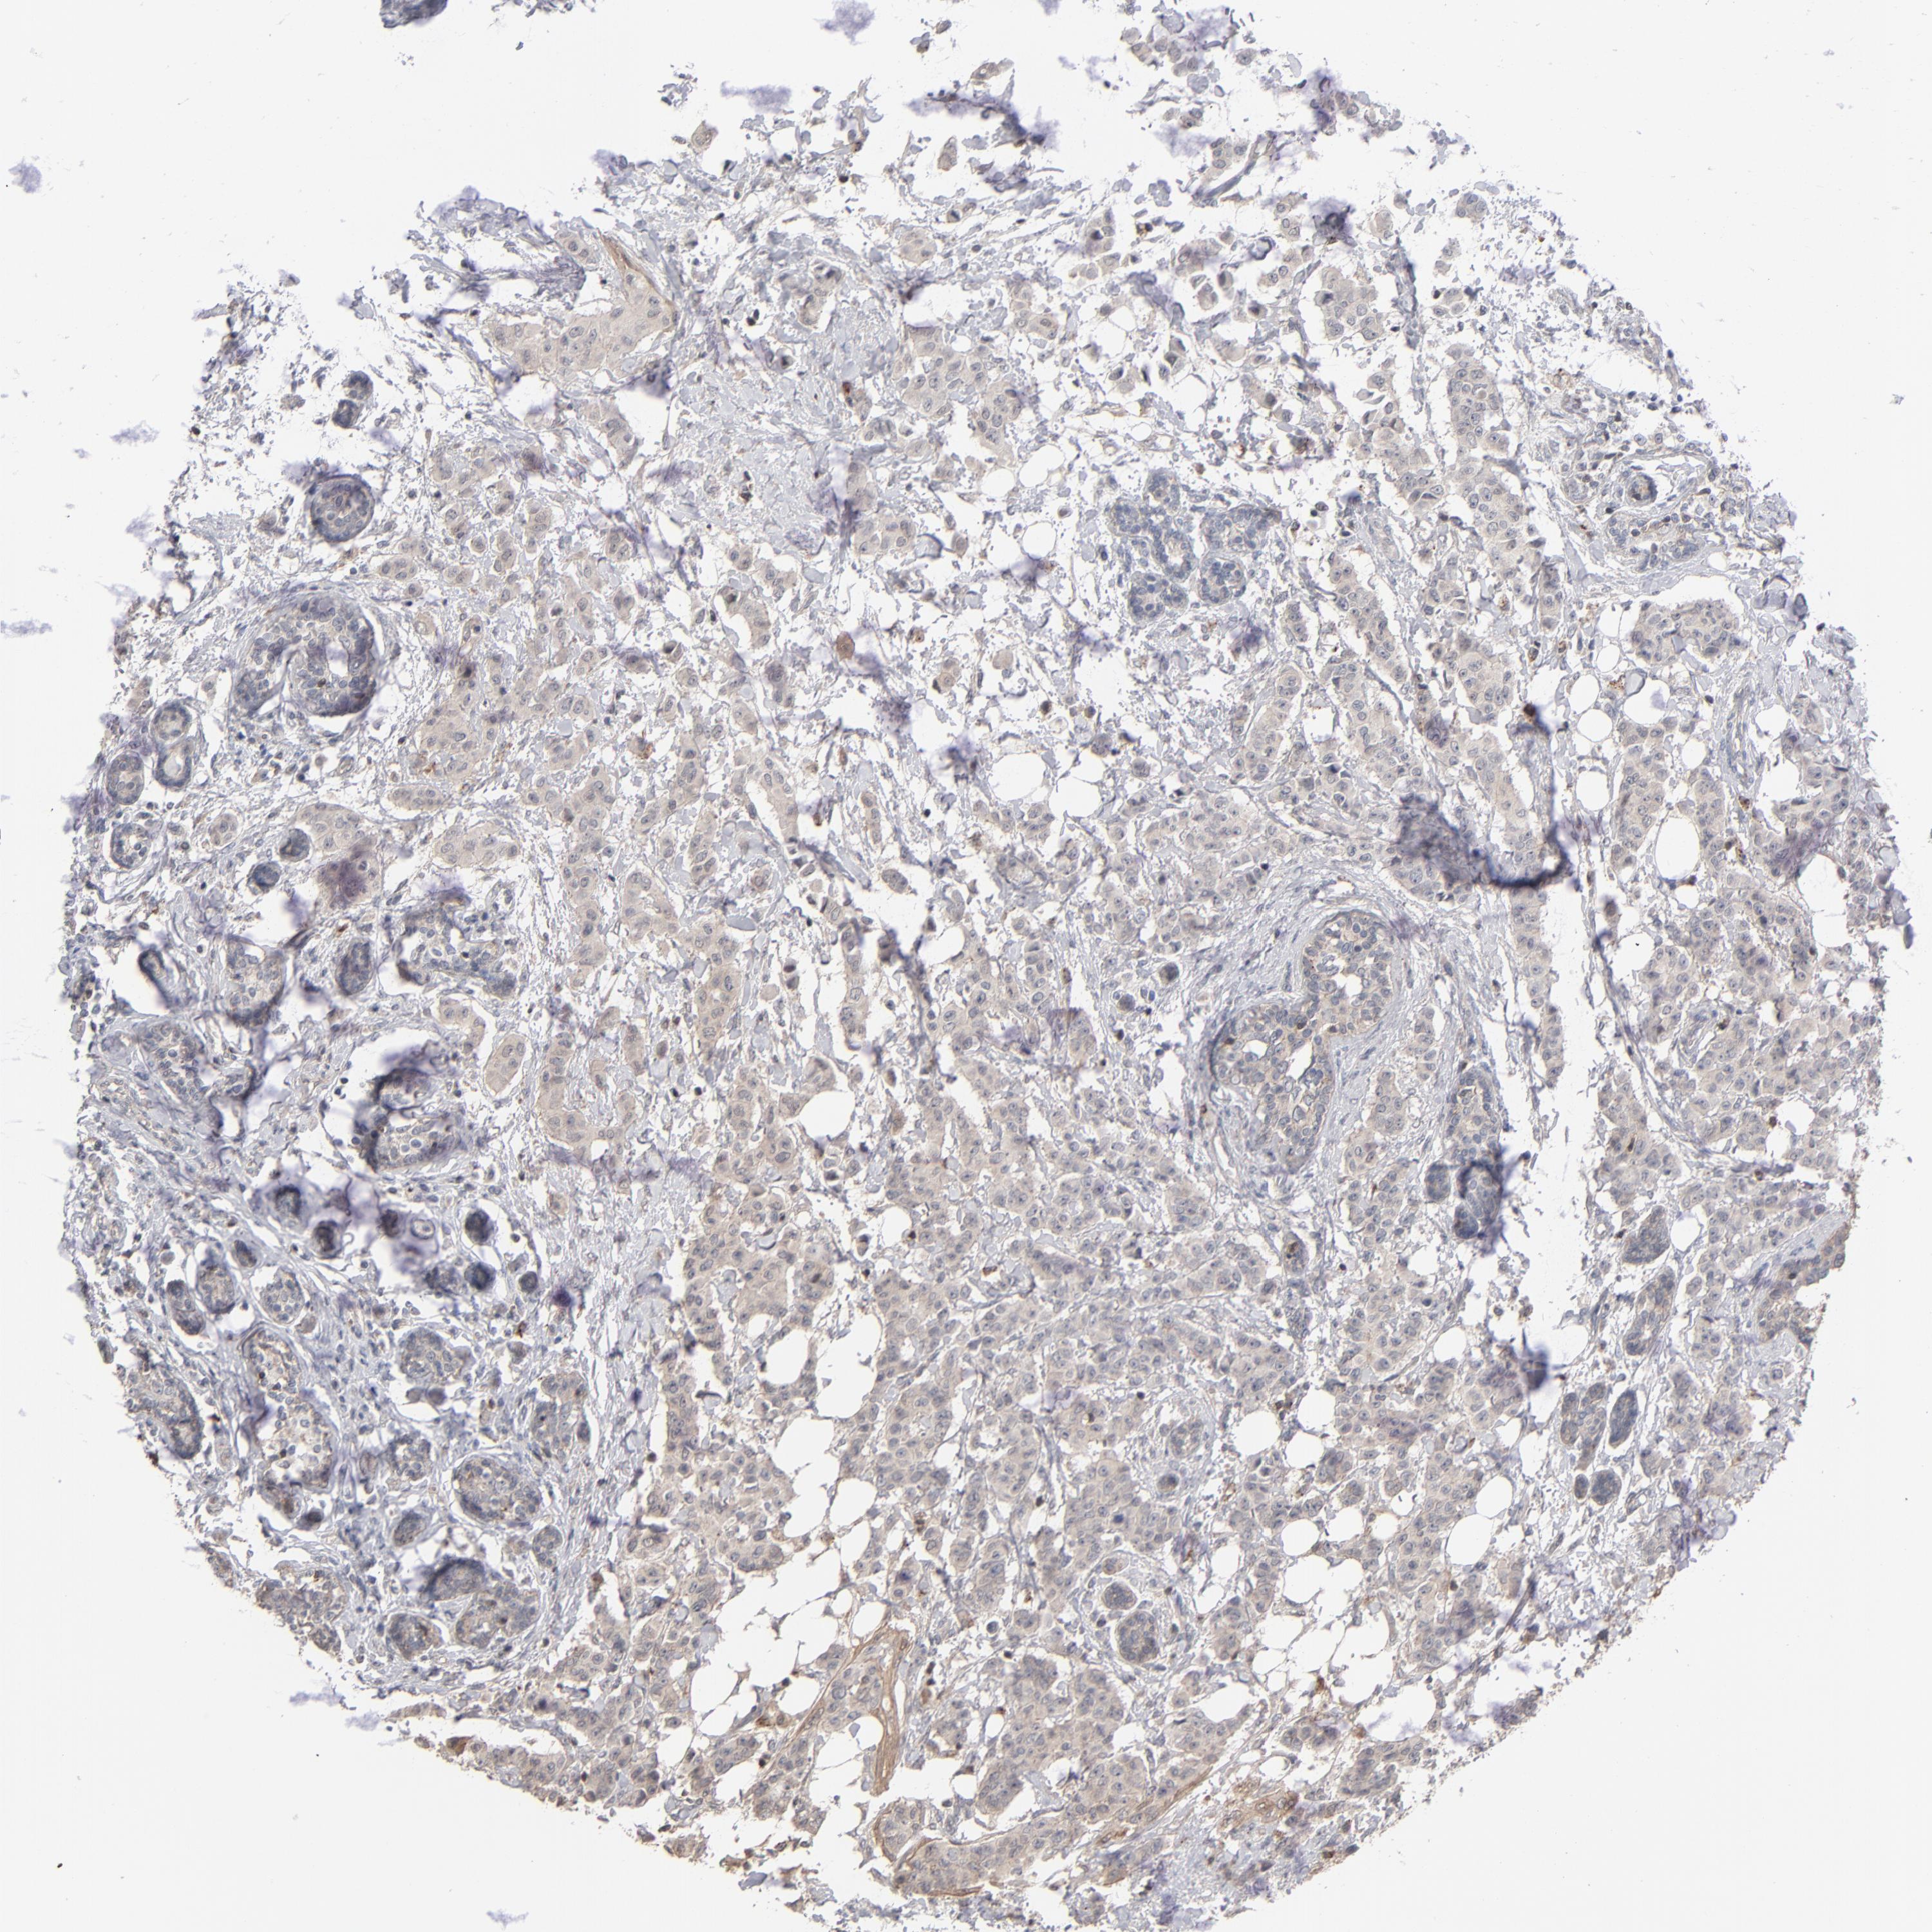

CANCER BREAST CANCER Show tissue menu

BRCA TCGA BRCA VALIDATION PROTEIN EXPRESSION